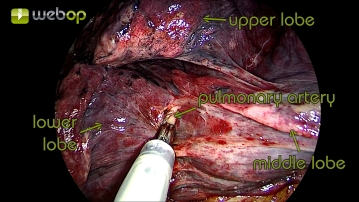

Präparation des Lappenspalts mit Darstellung der Pulmonalarterie

Nach Darstellung der Pulmonalaterie können die Parenchymbrücken schrittweise disseziert werden. Hierbei muss immer die Pars interlobaris der Pulmonalarterie dargestellt und stumpf abgeschoben werden, bevor das Gewebe oberhalb durchtrennt werden kann. So wird die Pulmonalarterie über einen längeren Abschnitt dargestellt und die Gefäßabgänge und die Mittellappenarterie können besser identifiziert werden